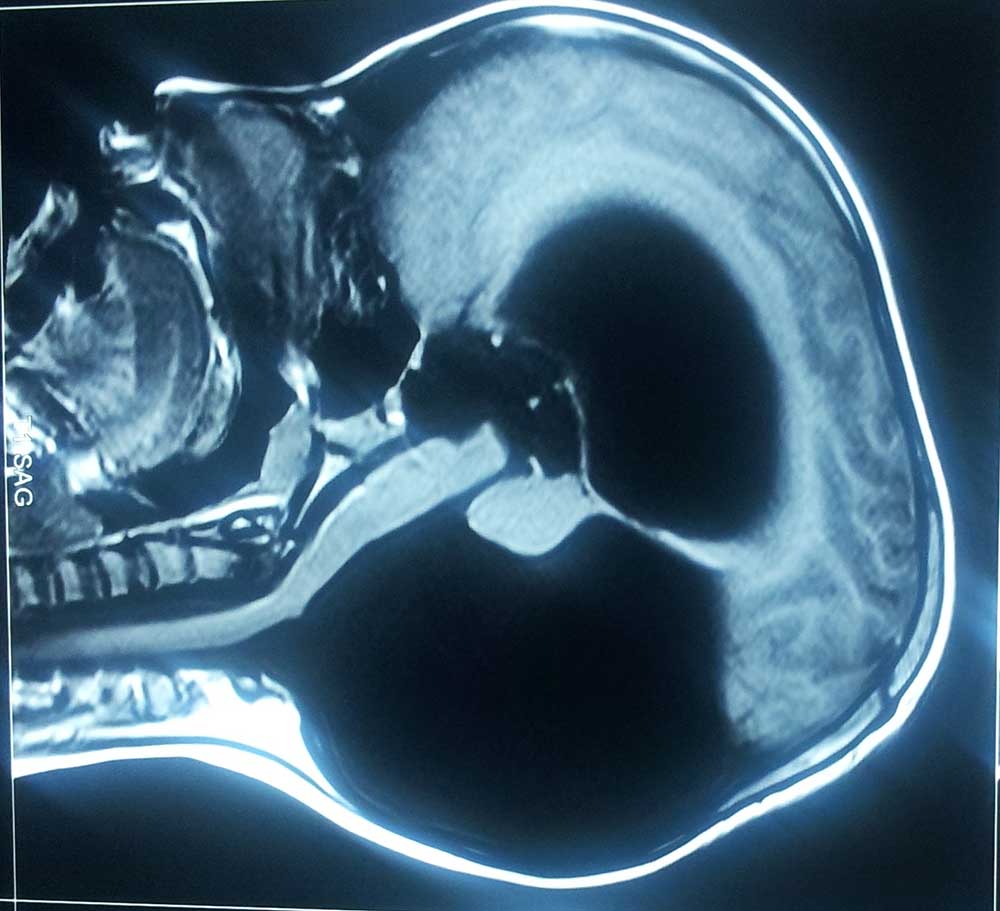

dandy walkar pre op mri

• dandy walkar pre op mri

preop mri

• preop mri